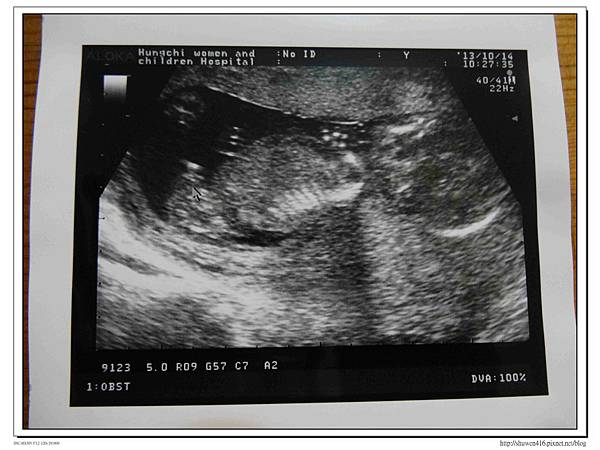

上回照胎兒透明頸帶時剛滿12W5D,主檢的醫師告知性別似乎還不確定,當下也不是很在意,因為不管生男生女都是自己的寶貝呀!此次產檢安排在上午,全家老小一起來,大家都想看看安寶寶,尤其小安安更是期待,整個照超音波的過程中更是目不轉睛盯著螢幕,醫生告師羊水量頗佳,因此臍帶會在羊水中漂浮著,不貼近寶寶的身體較不會發生臍帶繞頸的危險,繼續好好養胎保持下去,安寶寶此時似乎正在睡覺,手腳只是輕微的動了幾下,接著唐醫師很熱心的把螢幕箭頭指向性器官,很確定的公布安寶寶是個弟弟喔!

哇!我上輩子的小情人出現了,難怪這次懷孕症狀和上一胎截然不同,偶爾臉上會長出痘痘,噁心孕吐感也比以往強烈,直到最近採用飯水分離飲食法才整個改善許多,肚子變大的速度較慢,幾乎是往前長大,哈~這下可以來準備出清安安姊姊穿不下的衣服了。

老公說看到小雞雞在羊水中飄動,覺得很神奇XDDDD!!